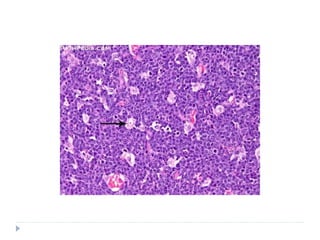

HISTOPATHOLOGY

 Monoclonal proliferation of B lymphocytes

 Lesion invades as broad sheets of tumour cells

 Tumour cells exhibit round nuclei with minimal

cytoplasm

 Each tumour nucleus has prominent nucleoli

 Numerous mitoses are seen

 At low power magnification: STARRY SKY PATTERN

is often appreciated

 STARRY SKY PATTERN

 Phenomenon that is caused by the presence of

macrophages within the tumour tissue

 Macrophages have abundant cytoplasm which

microscopically appears less stained in comparison with

the surrounding cells

 These macrophages also contain phagocytic debris

 THE MACROPHAGES THUS, STAND OUT AS STARS

SET AGAINST THE NIGHT SKY OF DEEPLY

HYPERCHROMATIC NEOPLASTIC LYMPHOID CELLS